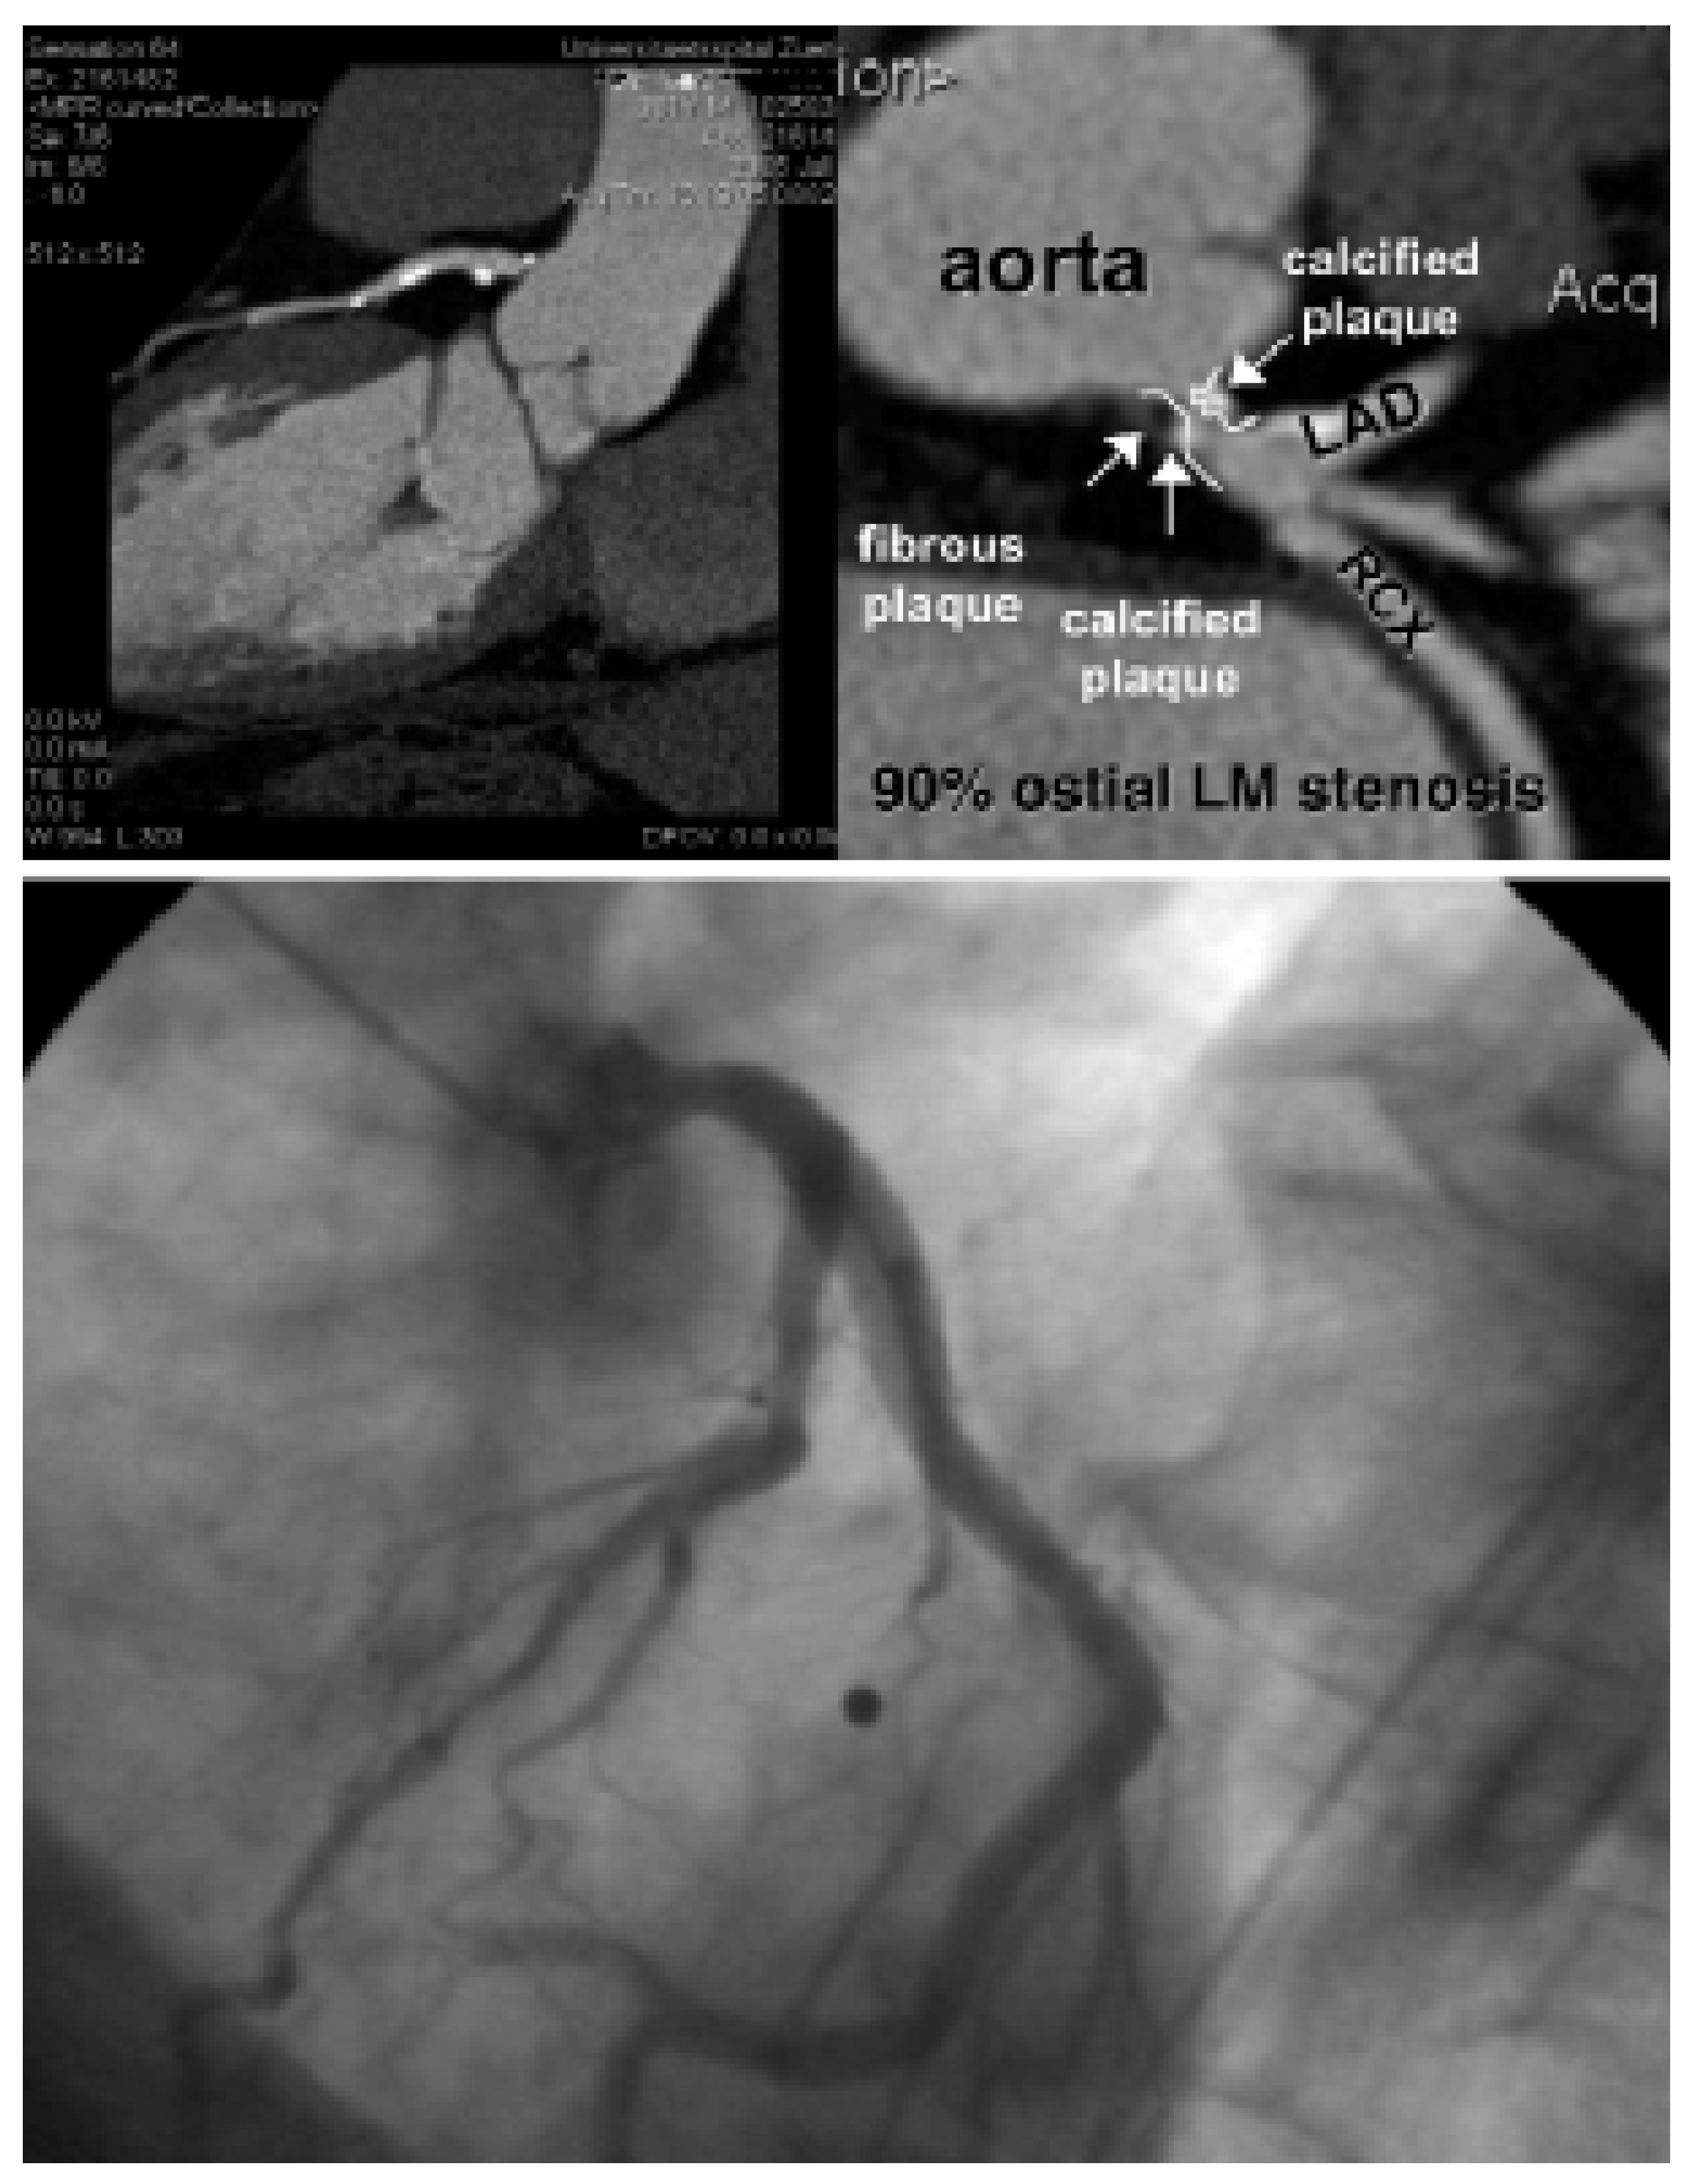

Abbildung 4. Darstellung von einer multiplanar rekonstruierten 64-Zeilen-CT-Koronarangiographie bei einem 81jährigen Patienten mit atypischen Thoraxschmerzen (oben). Im CT wurde eine schwere (ca. 90prozentige) ostiale, verkalkte Stenose des Hauptstammes vermutet (oben rechts). Die invasive Abklärung zeigte nur eine leichte Läsion ohne hämodynamisch relevante Einengung (unten).

Verkalkungen der Herzkranzgefässe beeinträchtigen allerdings auch erheblich die Darstellung des Lumens in der computertomographischen Angiographie (Abb. 2). Somit lässt sich in stark verkalkten Gefässen meist nicht sagen, ob es sich nur um ein krankes, d.h. arteriosklerotisch verändertes Koronarsegment handelt, oder ob es auch hämodynamisch relevant eingeengt ist. Vor allem bei älteren PatientInnen und solchen mit Diabetes und/oder Niereninsuffizienz, welche ausgeprägte Verkalkungen aufweisen, ist daher keine schlüssige Beurteilung des Lumens möglich. Zudem kann die EKG-getriggerte Untersuchung bei hoher Herzfrequenz, bei Vorhofflimmern und anderen Rhythmusstörungen, die bei etwa 5% der Patienten zu finden sind, nicht durchgeführt werden. Schliesslich sollte bei Patienten mit schwerer Herzinsuffizienz die Volumenbelastung durch das Kontrastmittel in Betracht gezogen werden. Auch durch Stents verursachte Artefakte stellen ein diagnostisches Problem dar (Abb. 3). Obschon die neuesten CT-Geräte sehr genau die Stent-Länge und den Durchmesser erfassen können, ist eine sichere Beurteilung des Lumens in vielen Fällen noch nicht möglich. Da bei der koronaren Herzkrankheit die Frage nach einer Intervention im Vordergrund steht, sei es eine kathetertechnische Stent-Implantation oder eine Bypass-Operation, ist die Erfassung von Koronarstenosen das Hauptziel dieser Untersuchungen. Entsprechend ist diese Einschränkung der Aussagekraft der computertomograpischen Koronarangiographie durch Gefässwandverkalkungen ein grosser Nachteil dieser Methode. Zusammenfassend ist daher der negativ prädiktive Wert der computertomographischen Koronarangiographie sehr hoch, d.h. bei fehlendem Nachweis von Kalzium und Einengungen lässt sich mit an Sicherheit grenzender Wahrscheinlichkeit eine koronare Herzkrankheit ausschliessen. Der positive prädiktive Wert behandlungsbedürftiger Koronarstenosen ist aber vor allem in der älteren Population, in welcher die koronare Herzkrankheit besonders häufig ist, immer noch stark eingeschränkt (Abb. 4). Unseres Erachtens können momentan wichtige klinische Entscheidungen (wie z.B., ob ein Patient aufgrund des Koronarbefundes mittels ACBPOperation oder PCI behandeln werden muss) nicht ausschliesslich anhand des CT-Befundes gefällt werden. Das Vorhandensein von Gefässverkalkungen hat den Einsatz dieser vielversprechenden Technik auch in anderen Gefässabschnitten (wie in den Karotiden [8,9]) beschränkt.